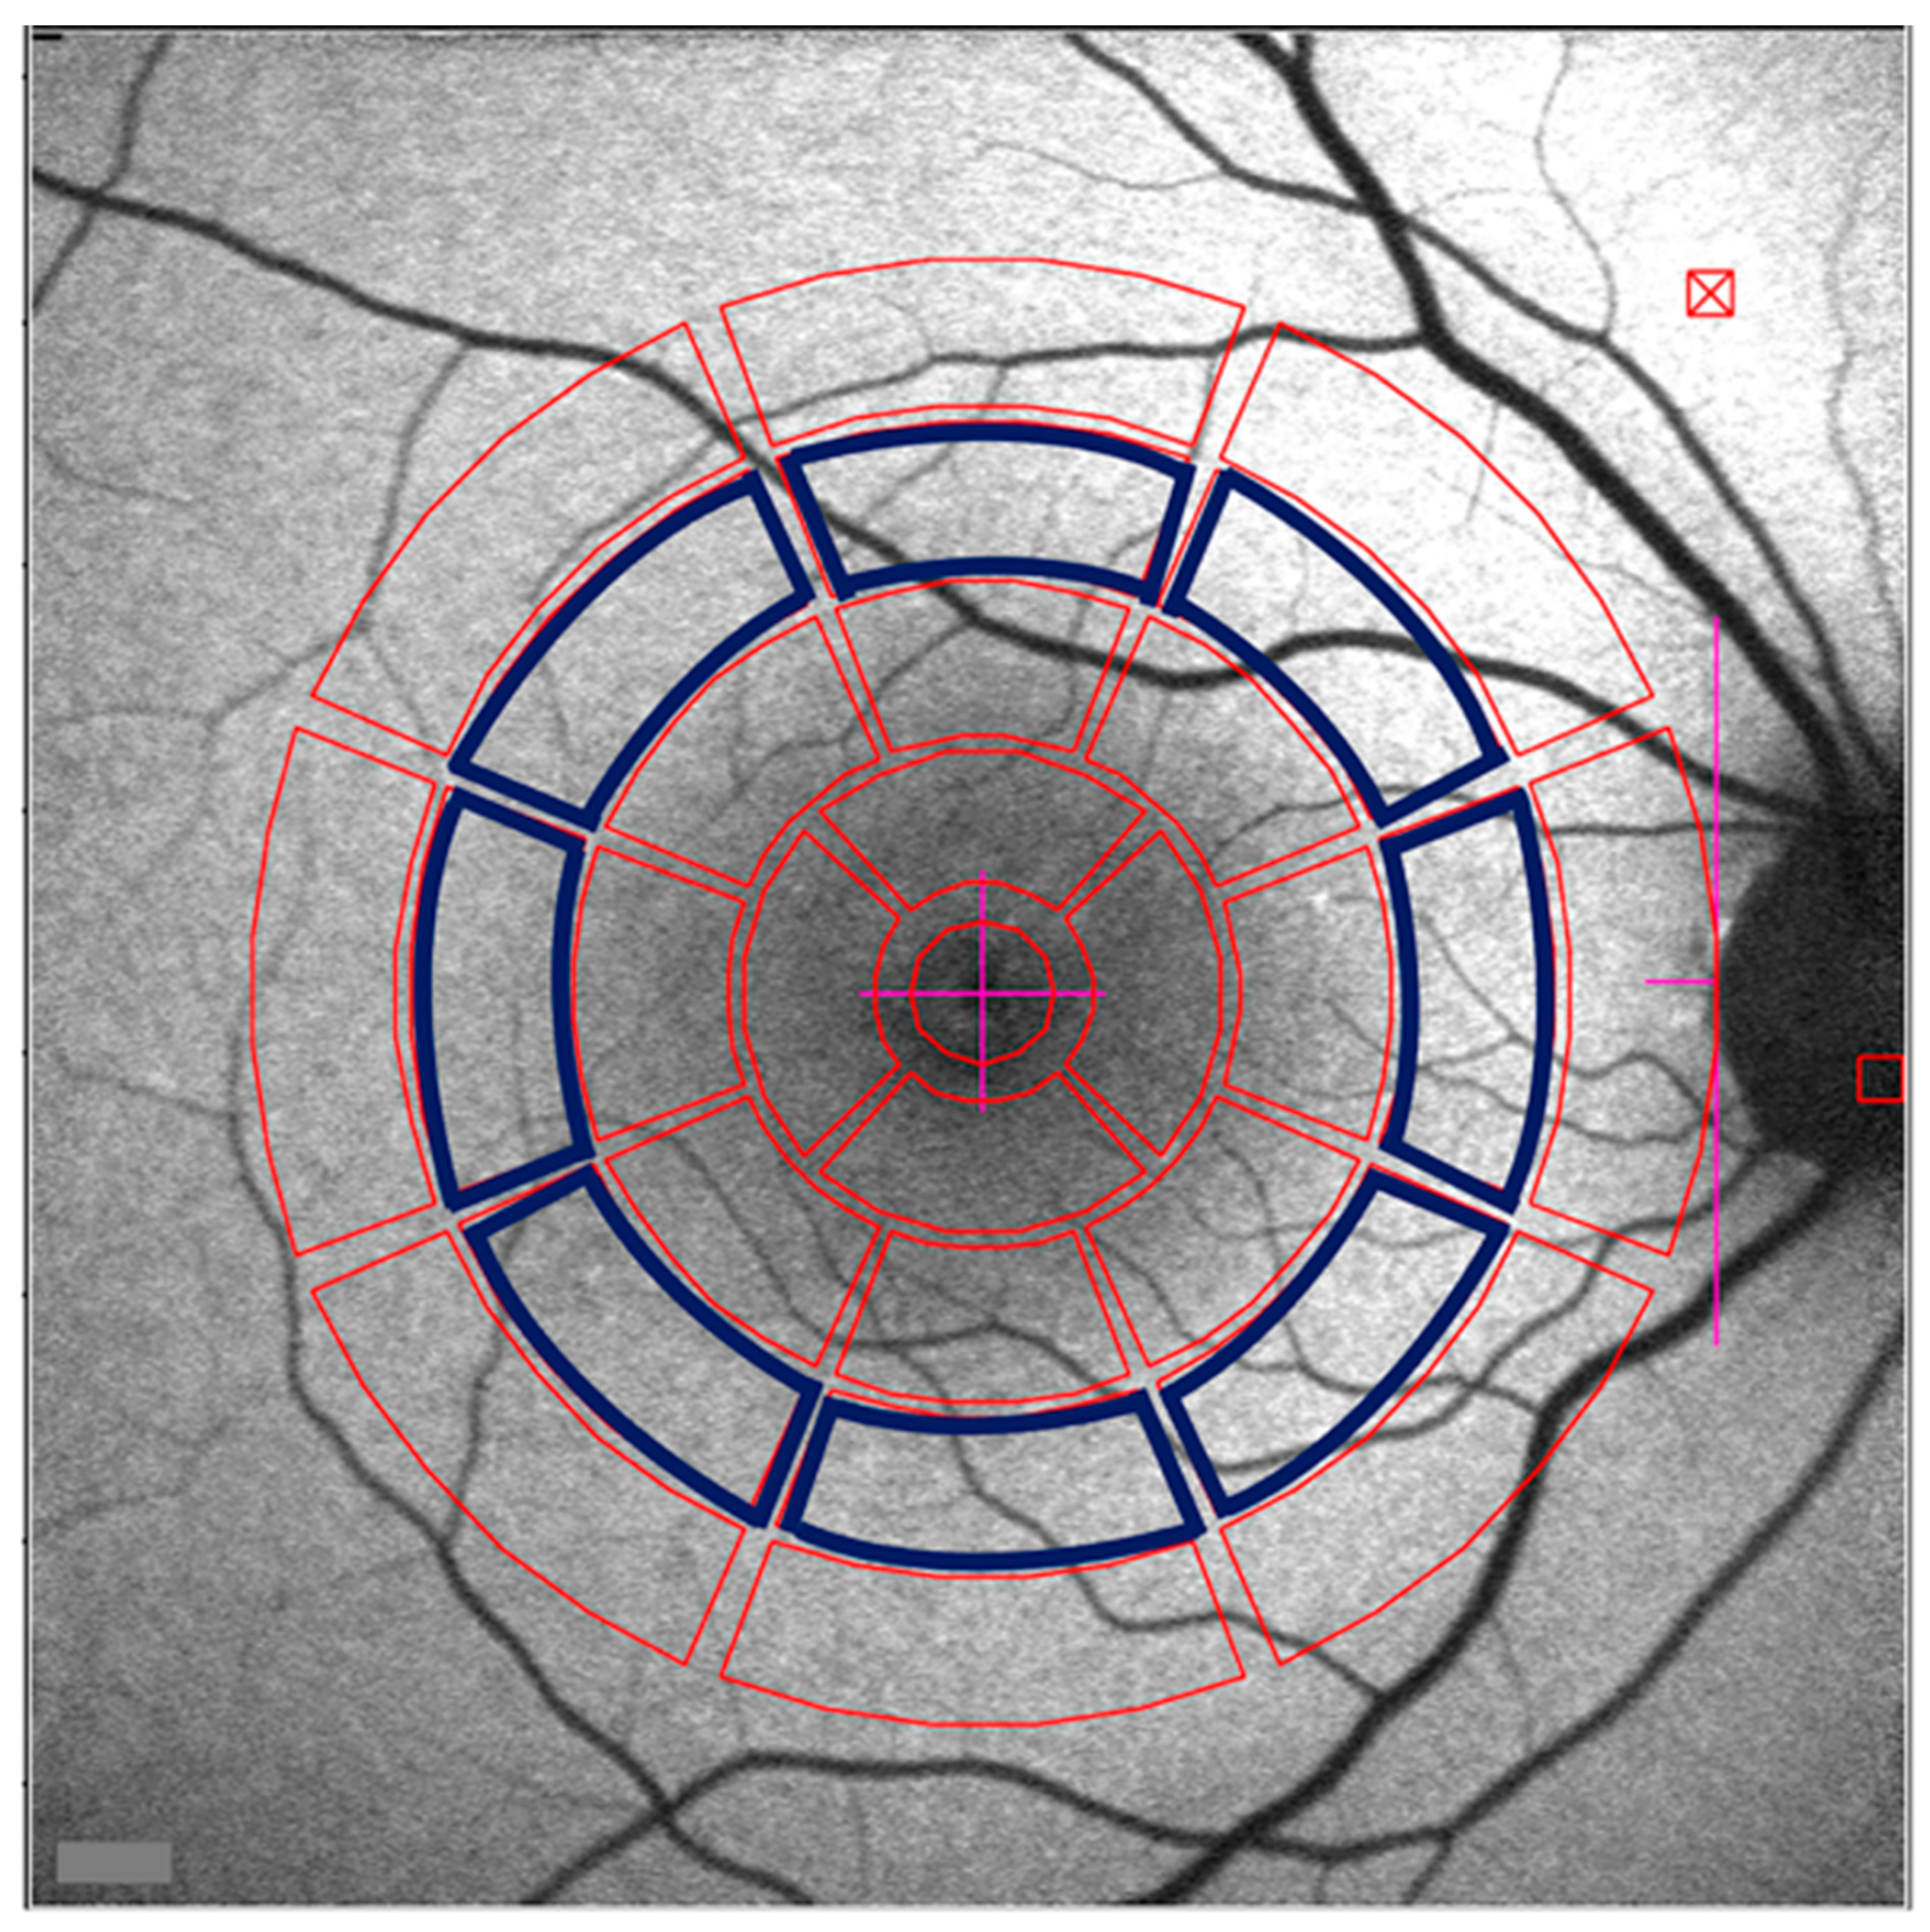

- Han, L.; de Carvalho, J.R.L.; Parmann, R.; Tezel, T.H.; Chang, S.; Sharma, T.; Sparrow, J.R. Central Serous Chorioretinopathy Analyzed by Multimodal Imaging. Transl. Vis. Sci. Technol. 2021, 10, 15. [Google Scholar] [CrossRef] [PubMed]

- Duncker, T.; Lee, W.; Jiang, F.; Ramachandran, R.; Hood, D.C.; Tsang, S.H.; Sparrow, J.R.; Greenstein, V.C. Acute zonal occult outer retinopathy: Structural and Functional Analysis Across the Transition Zone Between Healthy and Diseased Retina. Retina 2018, 38, 118–127. [Google Scholar] [CrossRef]

- Boudreault, K.A.; Schuerch, K.; Zhao, J.; Lee, W.; Cabral, T.; Yannuzzi, L.A.; Tsang, S.H.; Sparrow, J.R. Quantitative Autofluorescence Intensities in Acute Zonal Occult Outer Retinopathy vs Healthy Eyes. JAMA Ophthalmol. 2017, 135, 1330–1338. [Google Scholar] [CrossRef]